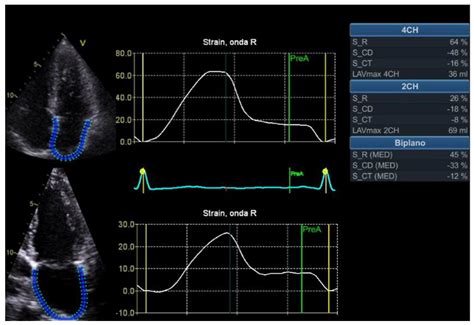

Research Story Tip: Obesity Weakens Heart Muscle in Patients with a

Research Story Tip: Obesity Weakens Heart Muscle in Patients with a ...